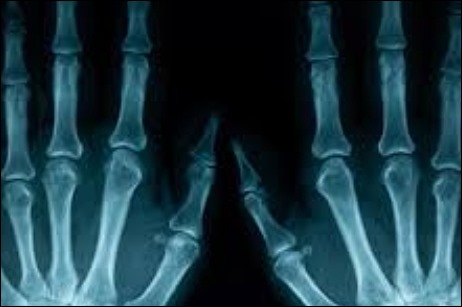

세 번째 원인은 류마티스 관절염입니다. 류마티스류머티즘 관절염이란, 정확한 원인이 아직까지 밝혀지지 않은 관절염인데, 유전적인 원인, 스트레스, 면역성 약화로 인해 생길 수 있는 질병 중 하나라고 합니다. 류마티스 관절염이 생기게 되면 손가락 관절에 심각한 손상을 입을 수 있으며, 손가락이 휠수도 있고 모양이 변형되는 특징도 가지고 있다 합니다.